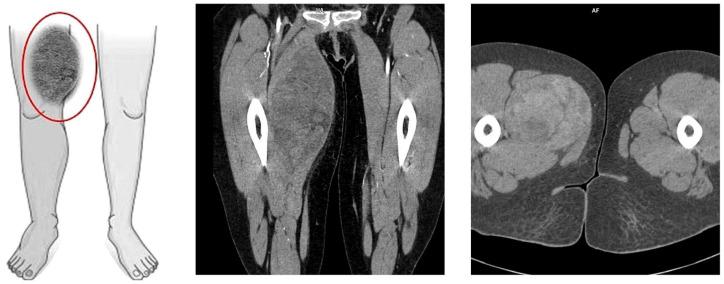

We report the case of a 36-year-old female patient on the 11th day of the puerperium after a cesarean section. The patient presented to the gynecology ward owing to the sudden appearance of a tumor in the medial part of her right thigh. The lesion was non-painful, mobile, soft, approximately 20 cm in diameter, and protruded above the level of the rest of the thigh surface. A suspicion of hematoma was raised. The final diagnosis was high-grade MLPS.